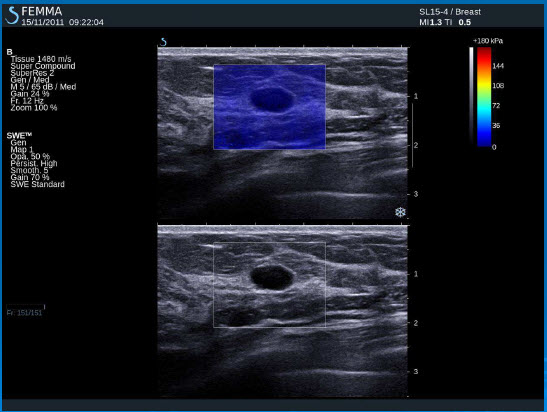

Normální tkáň prsu

Cysty